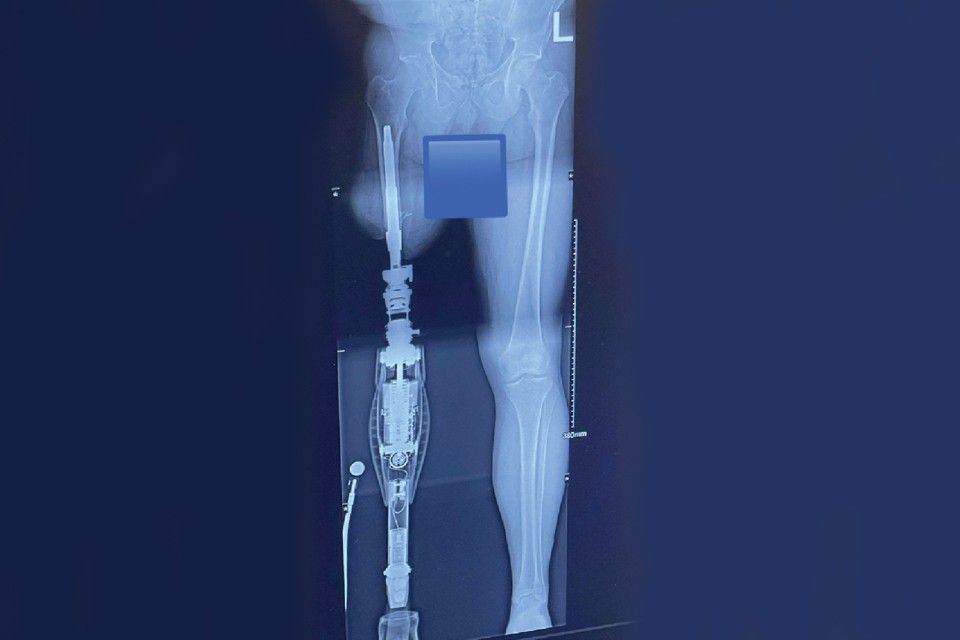

Osseointegration is now an advanced reconstructive surgery technique for amputees. The implant connects directly with the bone of the residual limb for the purpose of better body awareness and superior balance and gait. The procedure inserts a titanium implant into the marrow space of the bone. The rod becomes integrated over time to become part of the bone. The other end of the implant extends through the soft tissue for direct attachment to the prosthetic device.

He also uses a microprocessor knee, the Genium X3, and with the osseointegration and a brand-new leg he jokes that his “honey-do” list has doubled in size because his wife knows he can do a bunch more things than he could before osseo.